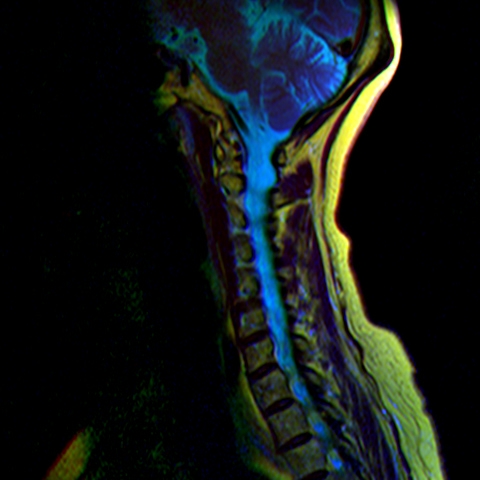

Color MRI of the Lumbar spine with extruded disc

Color MRI of the Lumbar vertebrae with extruded disc bit.ly/Color_MRI

- T1W FSE in red channel

- T2W frFSE in green channel

- STIR in blue channel.

- Yellow: Orange

- Water: Green-Blue

- Muscles: Purple